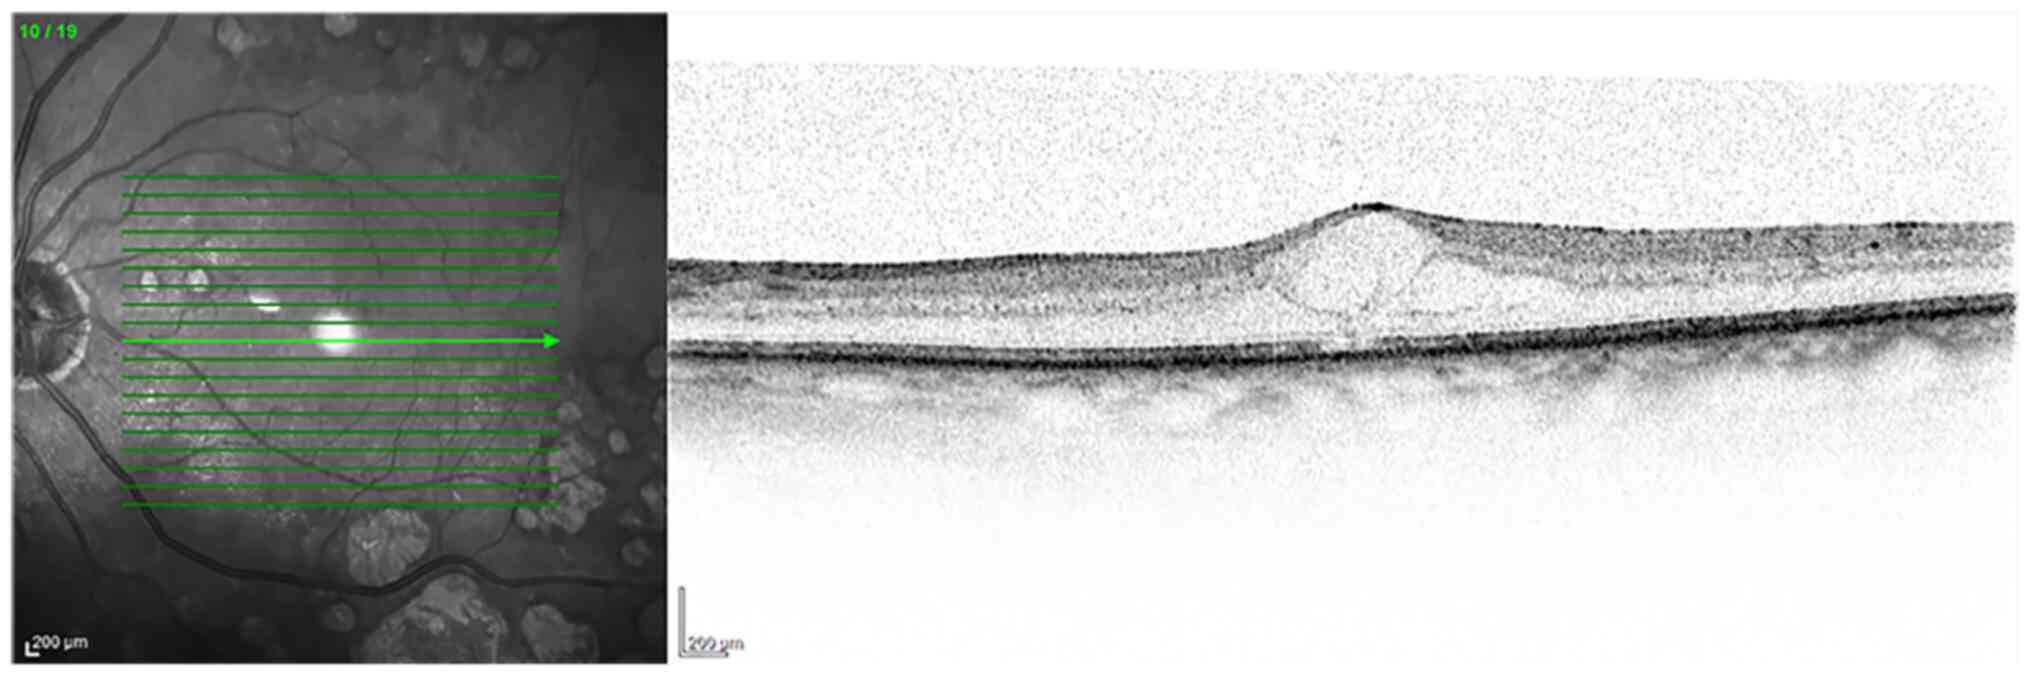

Figure 2

OCT. Wet age-related macular degeneration with choroidal neovascularization. Subretinal fluid and fibrovascular pigment epithelial detachment were also evident on the OCT. Diagnostic images provided by Professor M. Nebbioso. OCT, optical coherence tomography.